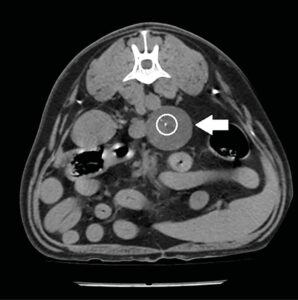

En estudios de TC sin contraste los feocromocitomas se observaron con valores más altos de Unidades Hounsfied (UH) con una atenuación media de 44,5 UH mientras que, en los adenocarcinomas, se observaron valores precontraste más bajos28,29. Esto puede deberse a que estos últimos se asocian con una mayor necrosis del parénquima o a que los feocromocitomas presentan con más frecuencia hemorragia intraparenquimatosa29. La angio-TC trifásica puede ayudar también a la diferenciación de las masas adrenales: se ha descrito que los feocromocitomas presentan una rápida captación de contraste en la fase arterial (imagen 6), mientras que los adenocarcinomas presentan un mayor realce en la fase venosa (imagen 7) y los adenomas un realce homogéneo en la misma fase32.

Imagen 6. Imágenes de TC plano transversal en ventana de tejidos blandos tras la administración de contraste en fases arterial (A) y venosa (B) de un feocromocitoma donde se observa un marcado realce en la fase arterial que disminuye y se vuelve más homogéneo en la fase venosa.